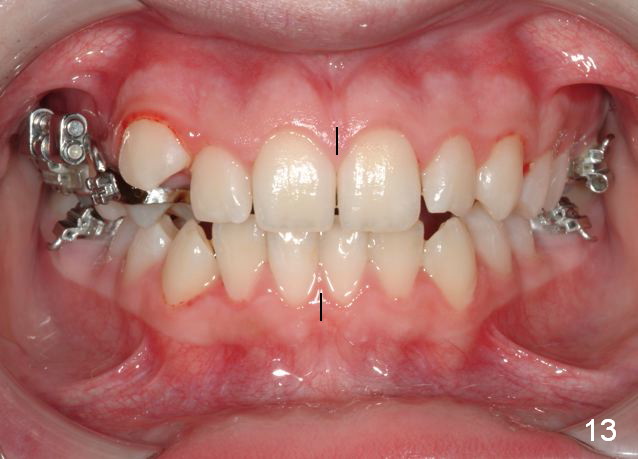

Rapid Molar Distalizer is placed (Fig.11). It is turned twice a week. UR6,7 are bodily distalized to Class I with gaining of the arch length 4 months 11 days later (Fig.12,14) without adverse effect on U midline (Fig.13). Final result?